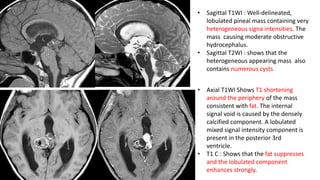

• Sagittal T1WI : Well-delineated,

lobulated pineal mass containing very

heterogeneous signa intensities. The

mass causing moderate obstructive

hydrocephalus.

• Sagittal T2WI : shows that the

heterogeneous appearing mass also

contains numerous cysts.

• Axial T1WI Shows T1 shortening

around the periphery of the mass

consistent with fat. The internal

signal void is caused by the densely

calcified component. A lobulated

mixed signal intensity component is

present in the posterior 3rd

ventricle.

• T1 C : Shows that the fat suppresses

and the lobulated component

enhances strongly.